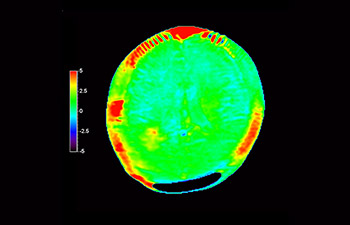

Astrocytoma

Brain astrocytoma, post-radiotherapy

with 3D APT

3D APT (Amide Proton Transfer) is a unique, contrast-free, brain MR imaging method addressing the need for more confident diagnosis in neuro oncology. 3D APT uses the presence of endogenous cellular proteins, to produce an MR signal that directly correlates with cell proliferation, a marker of tumoral activity. 3D APT can support trained medical professionals in differentiating low grade from high grade gliomas and, in differentiating tumor progression from treatment effect1.